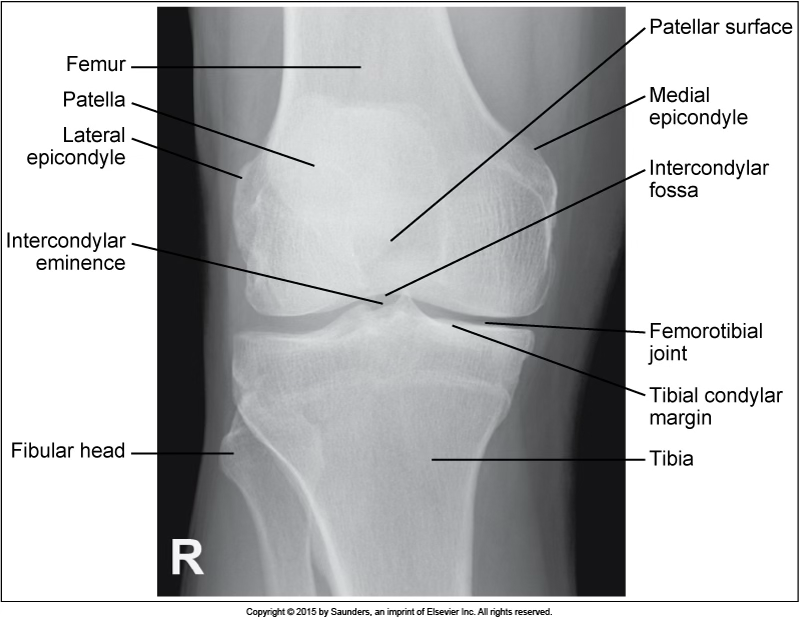

AP knee

accurate positioning